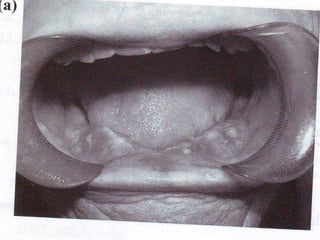

Con el Denosumab también se han

reportado casos de osteonecrosis de

la mandíbula.

Osteonecrosis de la mandíbula: 1:160 mil